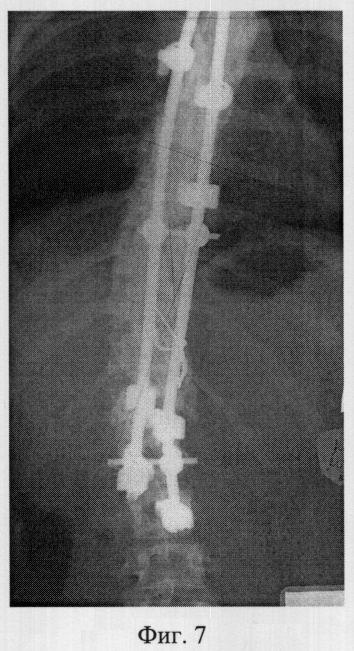

Фиг.8 – рентгенограмма в боковой проекции позвоночника больной M. после операции полисегментарной дорсальной коррекции и фиксации из заднего доступа;

Пример 2. Больная M., 15 лет, 12.10.04 поступила в клинику детской ортопедии СарНИИТО по поводу диспластического грудопоясничного правостороннего нестабильного прогрессирующего сколиоза III степени.

В СарНИИТО ей была выполнена рентгенография в стандартных проекциях: фасная (фиг.5) и боковая (фиг.6) рентгенограммы.

По фасной рентгенограмме определены показатели позвоночника:

– угол сколиотической деформации по Кобб: стоя – 63°, лежа – 48°;

– индекс стабильности по Казьмину – 0.87;

– определена протяженность дуги в 12 позвонков (от Th5 до L4),

– определена вершина деформации – Th11.

По рентгенограммам проведена оценка зрелости позвоночника: тест Риссера составил R-4, кольцевые апофизы тел позвонков не определяются на фоне тел по всей дуге искривления, что свидетельствует о завершенности роста больной.

В связи с протяженностью сколиотической дуги в 12 позвонков, локализацией центральной дуги в грудопоясничных отделах, завершенности роста больной сделан вывод о возможности проведения дорсальной коррекции сколиотической деформации и фиксации позвоночника из заднего доступа с созданием заднего спондилордеза.

Определили патологическую ротацию позвонков сколиотической дуги. Показатель патологической ротации на вершине деформации Th11 не превысил 43°, поэтому установка транспедикуллярных винтов не оправдана.

Заключение: необходимо проведение оперативной дорсальной коррекции и фиксации позвоночника двустержневой полисегментарной типа CDI «Horizon» фирмы «Medronic» с использованием дополнительных субламинарных проволочных петель

14.10.04 была выполнено запланированное оперативное вмешательство.

В послеоперационном периоде выполнены контрольные рентгенограммы: фасная фиг.6, боковая фиг.7. По фасной рентгенограмме определен угол остаточной деформации по Кобб – 23°, степень коррекции 40°, что составляет 64% от первоначальной деформации.